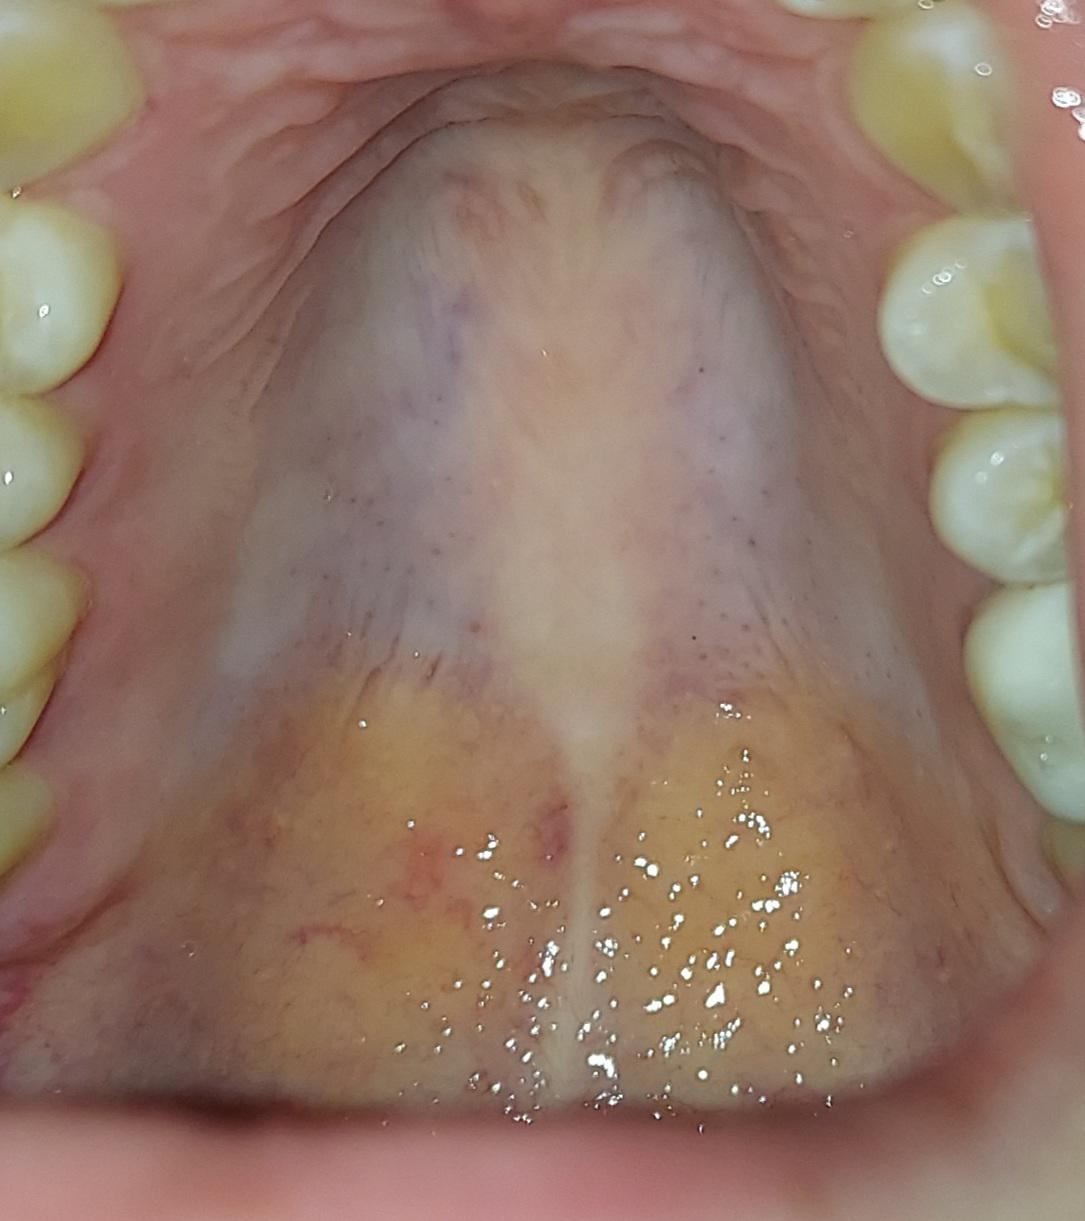

Discover the benefits of palate widening orthodontics for correcting narrow arches and improving dental alignment. Our expert guide explains how palatal expansion appliances work to resolve overcrowding, enhance breathing, and achieve a broader, healthier smile for both children and adults. Learn how this effective orthodontic treatment creates optimal space for proper bite function and long-term oral health.